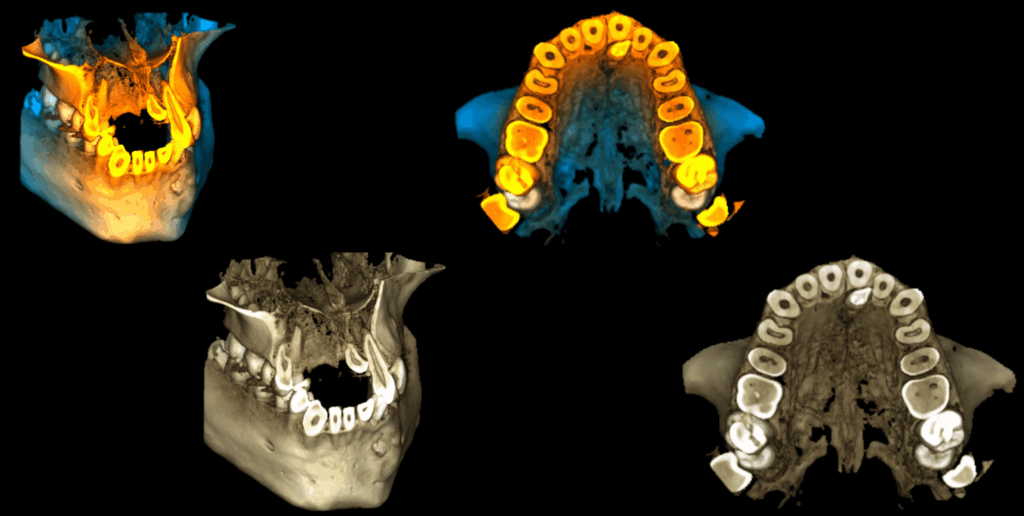

RECONSTRUCCIÓN 3D

- Pieza supernumeraria en línea media del maxilar superior (mesiodens).

- Odontoma en región canina inferior izquierda.

- Raíz adicional (radix paramolaris) en pieza 37.

- Raíz adicional (radix entomolaris) en pieza 46.